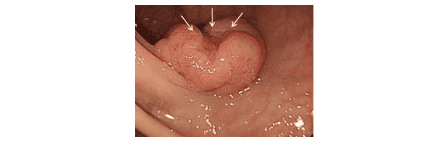

3. Đặc điểm của polyp ung thư hóa trên hình ảnh nội soi thông thường

Đặc điểm của một số polyp nghi ung thư hóa: bề mặt có khuynh hướng lan rộng, bề mặt polyp có loét hoặc viêm trợt, các nếp niêm mạc ruột hội tụ về phía polyp, polyp dạng “đặc”, polyp dạng lõm với phần trung tâm nhô lên.

Nguồn: Endoscopic features of submucosal deeply invasive colorectal cancer with NBI characteristics, S Saito et al. Endoscopic images of early colorectal cancer, Clinical Journal of Gastroenterology volume 8, pages353–359(2015)

Đối với những dạng hình ảnh như vậy, bác sĩ nội soi cần cân nhắc trước khi cắt polyp, vì có thể mức độ ung thư xâm lấn của polyp đã đến lớp dưới niêm, và việc cắt polyp qua nội soi không đảm bảo an toàn mặt ung thư.